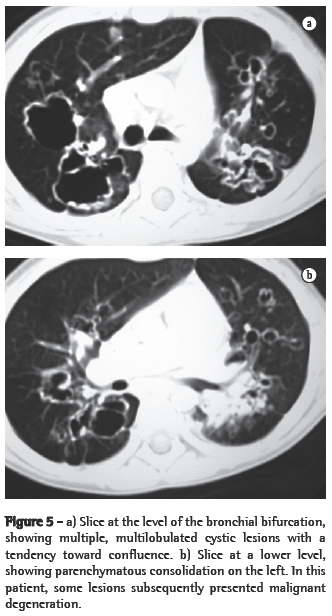

ResultsIn all eight cases, the CT scans revealed polypoid formations in the trachea. In one case, injury to one of the main bronchi was identified. Seven patients presented involvement of the pulmonary parenchyma. In all eight cases, there were cavitated polypoid lesions, with irregular internal borders and walls of various thicknesses, multilobulated in six cases and presenting confluence of the lesions in five (Figures 1 through 5). Solid nodules were seen in six patients. An air-fluid level was observed in only one patient. The lesions were predominantly in the lung bases in three patients and in the middle thirds in two, whereas they were evenly distributed in two. In one patient, the lesions were accompanied by a mass, and, in another patient, they were accompanied by consolidation. In the latter case (Figure 5), there was malignant degeneration in multiple lesions. Signs of air trapping were also observed in one case. There were no identified instances of lymph node enlargement or pleural effusion.

Chest X-rays are inferior to CT scans of the chest, especially those performed using spiral CT (volumetric acquisition), in the initial phases of pulmonary dissemination, due to the fact that CT better characterizes and allows better visualization of nodular tracheobronchial vegetation, Tomographic findings include focal or diffuse airway narrowing caused by the nodules. The nodules form on the mucosal surface, and their invasion into the lumen is best evaluated using CT.(3) These alterations are easily correlated with the disease when there is a clinical history of papillomatosis.(4) Other findings related to airway obstruction and accompanying infections are atelectasis, consolidations, air trapping and bronchiectasis.(2-4) In our sample, polypoid formations in the trachea were observed on all of the CT scans Seven patients presented involvement of the pulmonary parenchyma, characterized by cavitated polypoid lesions with irregular internal borders and walls of various thicknesses, with a multilobulated aspect and a tendency toward confluence. Solid nodules were seen in six patients. None of the patients presented lymph node enlargement or pleural effusion.